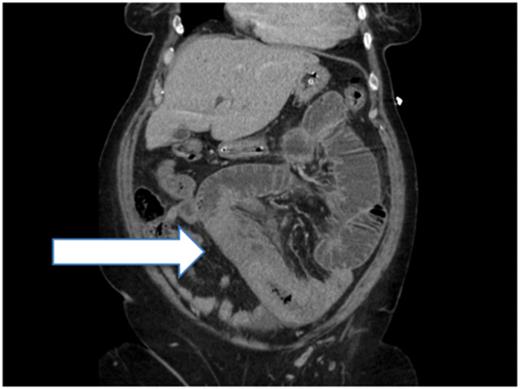

Laboratory investigations revealed an International Normalized Ratio (INR) of 10; she was anticoagulated with warfarin due to her atrial fibrillation. Initial imaging revealed dilated small-bowel loops on abdominal radiograph (Fig. 1).

Abdominal radiograph showing dilated small-bowel loops (Case 1).